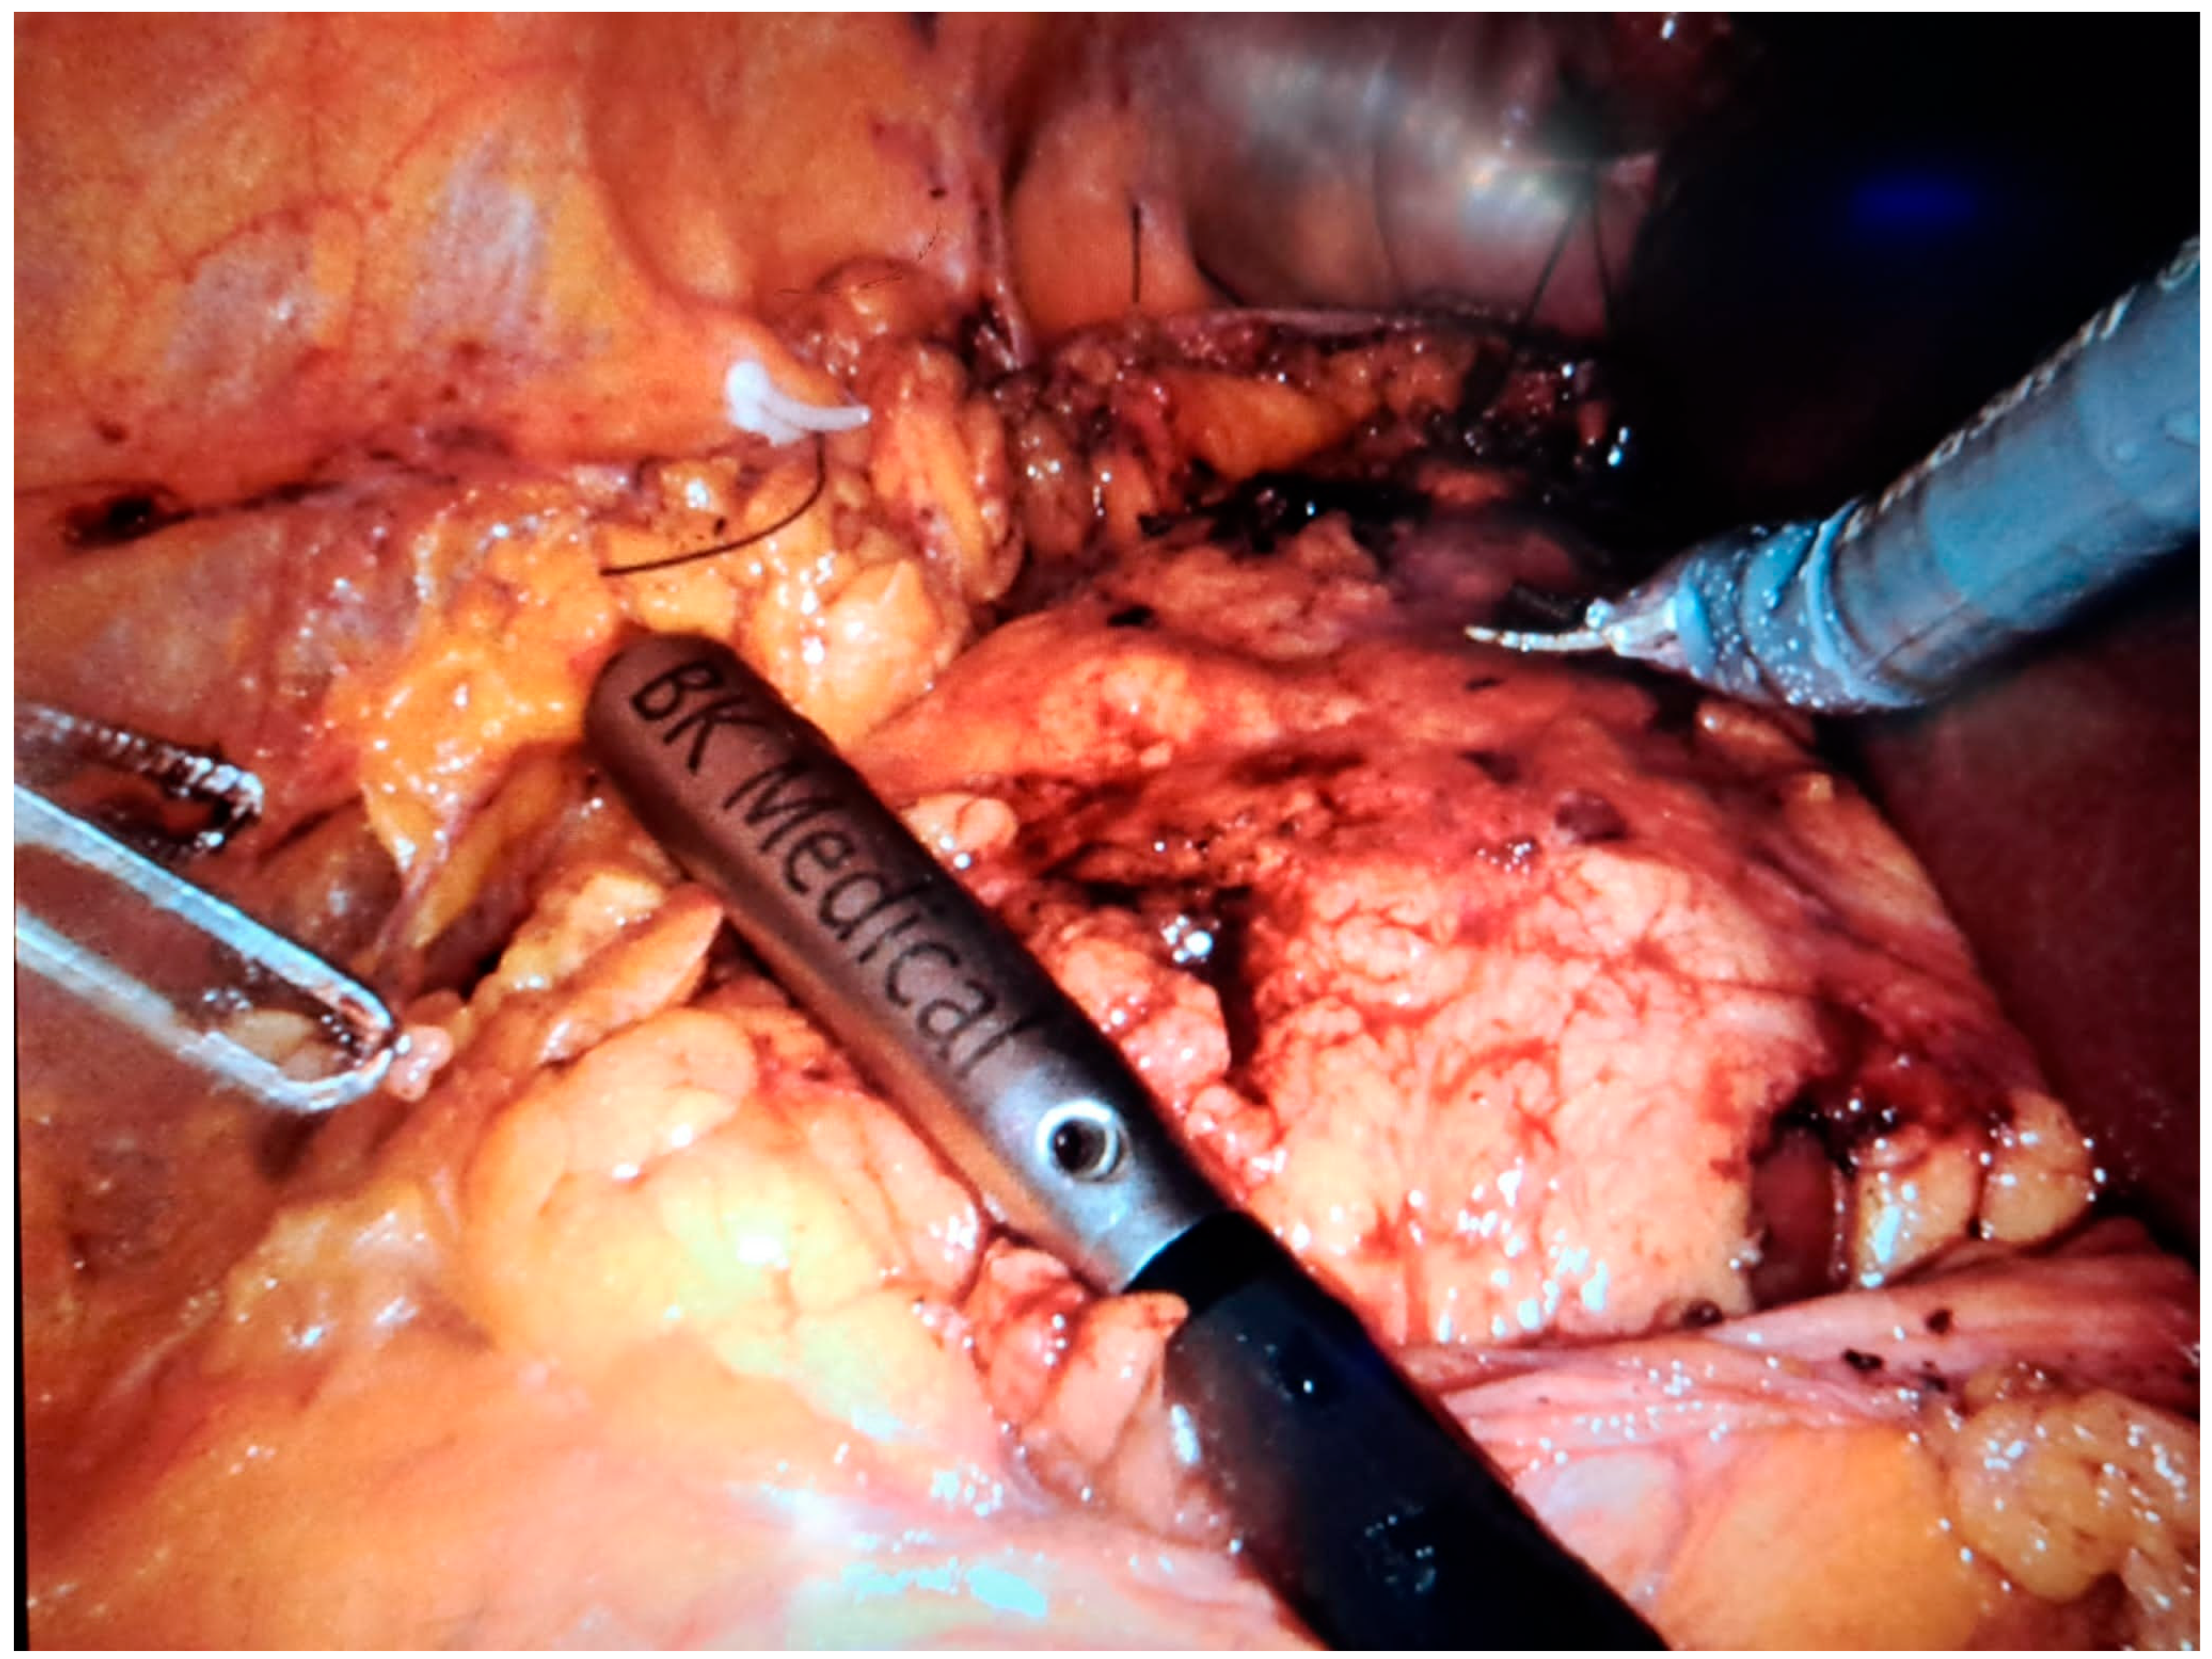

In robot-assisted laparoscopic surgeries, the I12C4f (9066) transducer (Figure 3, Figure 4 and Figure 5) was used, while in open surgeries, a linear soft-tissue probe compatible with the BK Medical 5000 system (BK Medical, Boston, MA, USA) was employed (Figure 6). Data were collected retrospectively and analyzed to compare image clarity, accuracy of tumor margin delineation, and intraoperative outcomes.

Figure 6. Intraoperative ultrasound—open surgical approach. (no tumor expression).